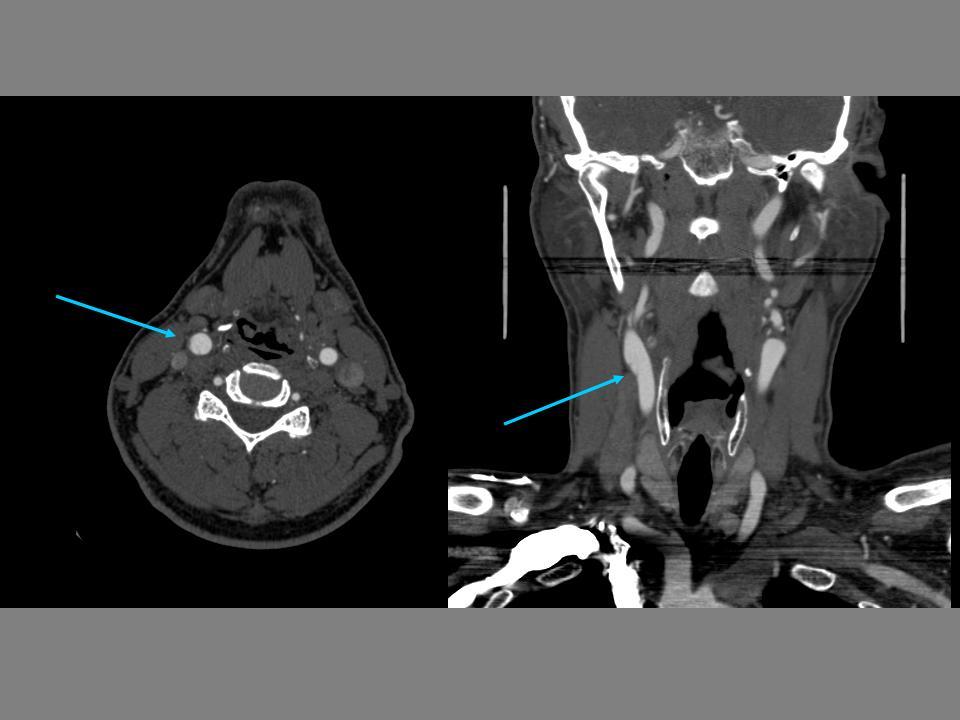

61 year old man

Presents with right arm and leg numbness and weakness and slurred speech. Symptoms lasted about 20 minutes and resolved

PMHx: type I diabetes, hypertension, and hyperlipidemia

Exam on presentation is normal

Had embolism from carotid artery let loose

microembolism from severe atherosclerotic carotid stenosis

***

Why isn’t cardioembolism as likely? – Doesn’t as easily get better (fewer TIA’s more

large strokes)

– With a shower of emboli, would expect to see in ALL territories (left and right, anterior and posterior)